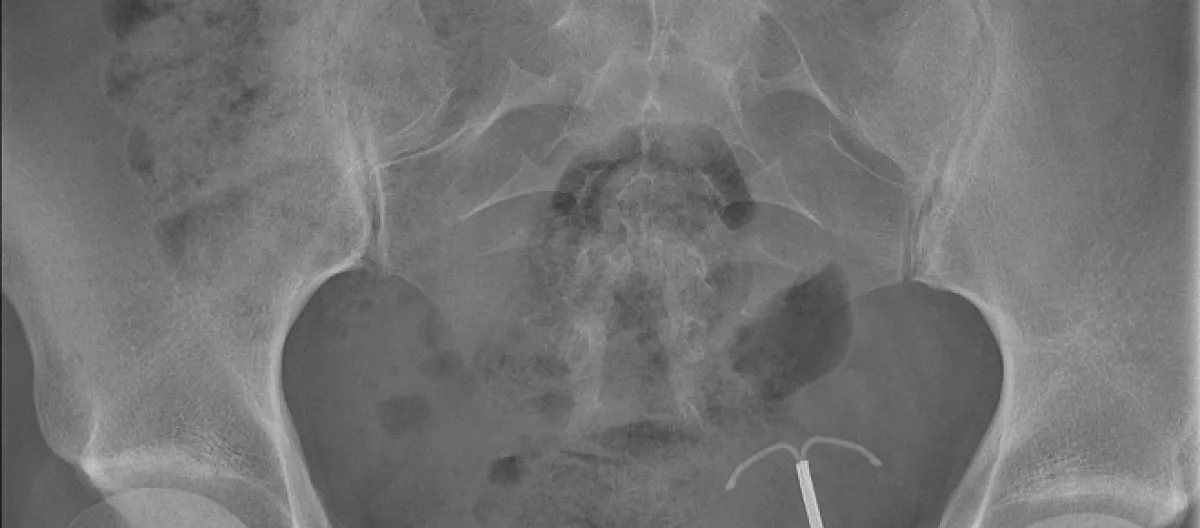

Results of the CT scan and X-ray